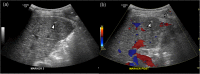

Objective: Stereotactic body radiation therapy (SBRT) for the treatment of a malignancy in the liver requires the perilesional implantation of fiducial markers for lesion detection. The purpose of this study is to evaluate the efficacy and safety of ultrasound (US) -guided marker implantation for SBRT.

Methods: We retrospectively reviewed 299, US-guided, intrahepatic fiducial markers implanted in 101 patients between November 2013 and September 2014. SBRT-planning CT images were analyzed to determine the technical success of the implantation, the mean distance between the tumor margin and the marker, with the ideal location of fiducials defined as the distance between a marker and a tumor less than 3 cm and the distance between markers greater than 2 cm according to the tumor conspicuity seen on gray-scale US and the artifact obscuring tumor margins. We also evaluated procedure-related major and minor complications.

Results: Technical success was achieved in 291 (97.3%) fiducial marker implantations. The mean distance between the tumor and the marker was 3.1 cm (S.D., 2.1 cm; range, 0-9.5 cm). Of 101 patients, 72 lesions (71.3%, 2.2 ± 1.0 cm; range, 0-3.0 cm) had fiducial markers located in an ideal location. The ideal location of fiducials was more common in visible lesions than in poorly conspicuous lesions (90.2% vs. 52.0%, P < 0.001). Seventeen markers (5.8%) developed beam-hardening artifacts obscuring the tumor margins. There were no major complications, although 12 patients (11.9%) developed minor complications.